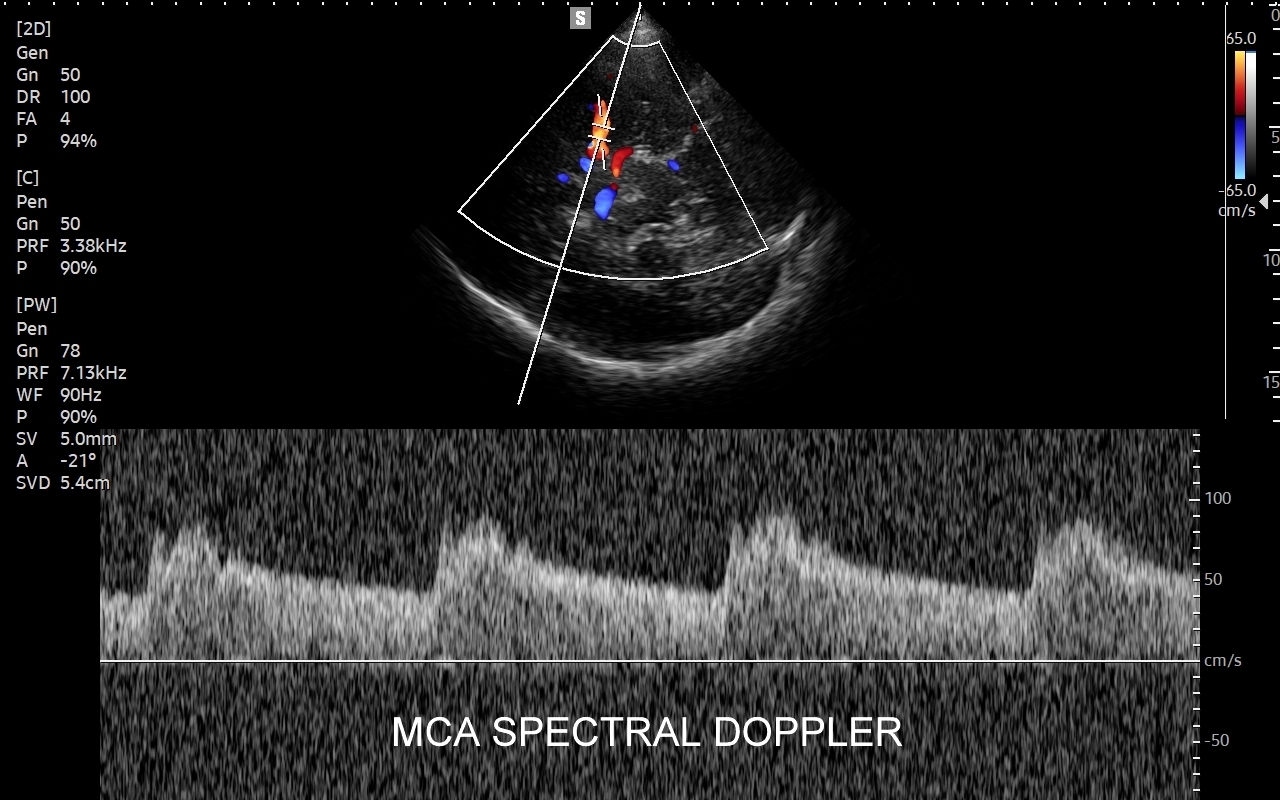

USG TCCD tętnic wewnątrzczaszkowych

Badanie USG Doppler tętnic wewnątrzczaszkowych (ang. TCCD, transcranial color-coded Doppler), nazywane także Dopplerem przezczaszkowym jest naturalnym rozszerzeniem i uzupełnieniem badania dopplerowskiego tętnic dogłowowych zewnątrzczaszkowych. Badanie polega na obrazowaniu przy użyciu dedykowanej sondy poprzez tzw. okno skroniowe czaszki głównych naczyń tętniczych mózgu, tj. koła Willisa, tętnic mózgowych przednich, środkowych i tylnych po obu stronach. Badanie TCCD umożliwia wykrycie wybranych wewnątrzczaszkowych patologii naczyniowych takich jak tętniaki, malformacje naczyniowe, zwężenia i niedrożności poszczególnych tętnic mózgowych, spazm naczyniowy, a także pozwala na ocenę kierunku przepływy krwi w kole Willisa mózgu, co  jest przydatne przy diagnostyce zespołu podkradania lub w ocenie po przebyciu udaru mózgowego.